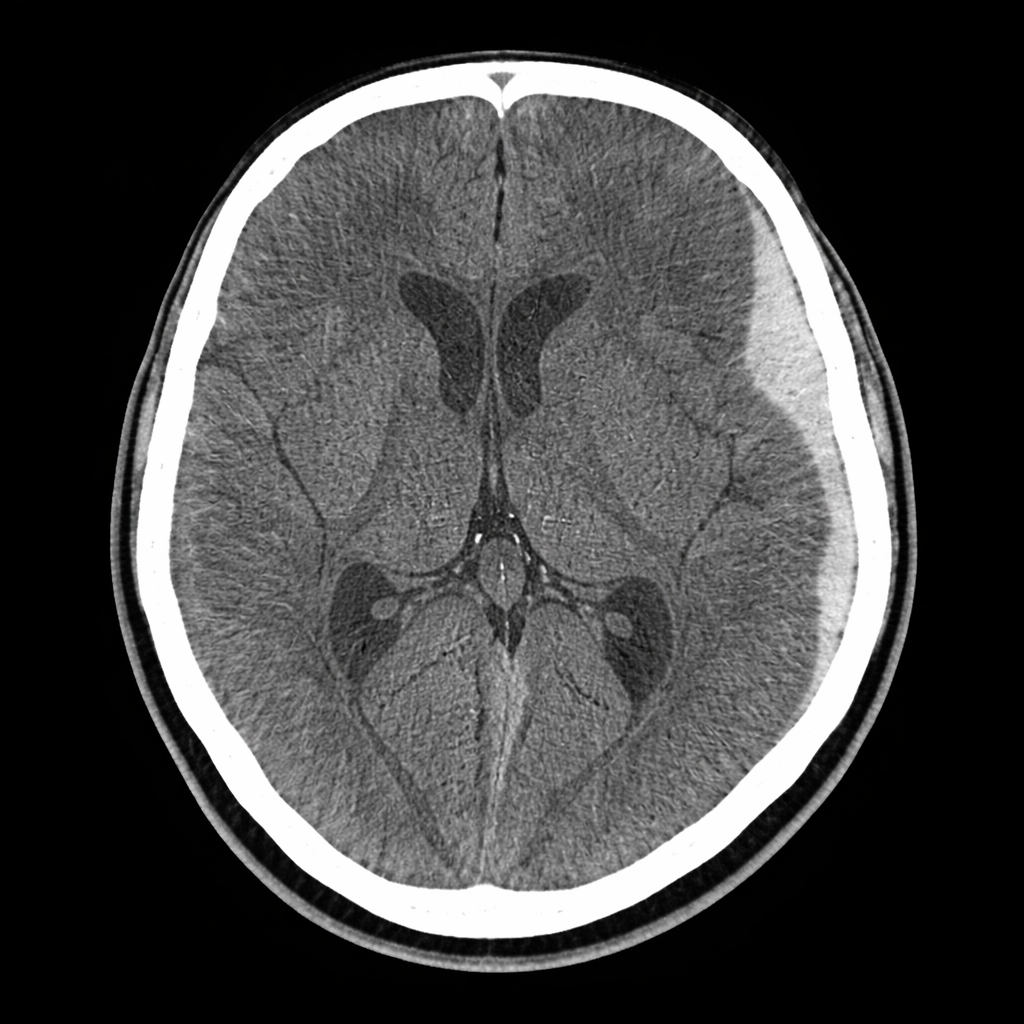

In Kincaid v. State, an eleven-month-old baby was dropped off at an in-home daycare appearing “alert and smiling.” Just a few hours later, the caregiver called 911 because the baby was unresponsive and foaming at the mouth. A CT scan revealed a large skull fracture, significant brain swelling, and a subdural hematoma on the left side of the brain. Doctors believed the injury occurred four to eight hours before the scan — placing it squarely during the child’s time in the caregiver’s home.

A newborn baby was found pale, struggling to breathe, and crying unusually loudly after sleeping on the couch between his father’s legs. He was diagnosed with subdural hemorrhages, bleeding in the lumbar spine, and retinal hemorrhages “too numerous to count.” A pediatric child-abuse fellow concluded the injuries were consistent with non-accidental trauma involving rapid acceleration and deceleration — commonly associated with abusive head trauma.

Some babies have medical conditions that make them more prone to developing subdural hematomas — bleeding between the brain and the skull — even without significant trauma. One example is Benign Enlargement of the Subarachnoid Space (BESS).

Because of this, they can develop chronic or recurring bleeding over time. Symptoms may appear suddenly, even though the underlying process has been developing for weeks or months.

These cases often show:

• Mixed old and new bleeding

• No skull fracture

• Little or no soft-tissue swelling

• No clear impact event

• Gradual or unexplained symptoms

This type of presentation is different from what doctors saw in Kincaid. Some babies also have genetic conditions or bleeding disorders that make them more likely to develop subdural hematomas without any abuse at all. Certain clotting disorders can cause blood vessels to bleed more easily. Other inherited conditions can affect how fragile a child’s blood vessels are or how their body responds to minor stress or pressure.